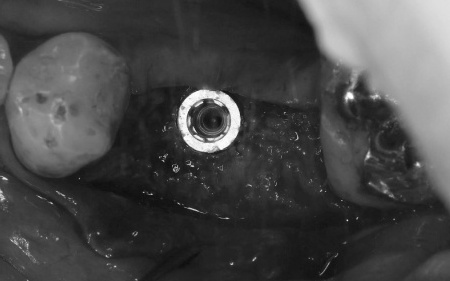

その後、傷の治癒が確認できたうえで、インプラントの埋入手術を実施しました。

インプラントの埋入後は、インプラントと骨がしっかりと結合するまで、さらに数ヶ月間経過観察を行います。

後日、インプラントと骨の結合を確認してから精密な型取りを行い、耐久性に優れた白い被せ物を作製しました。